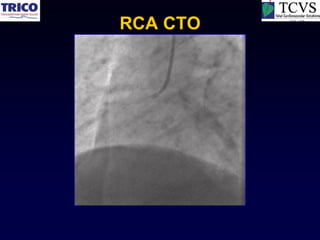

RCA CTO